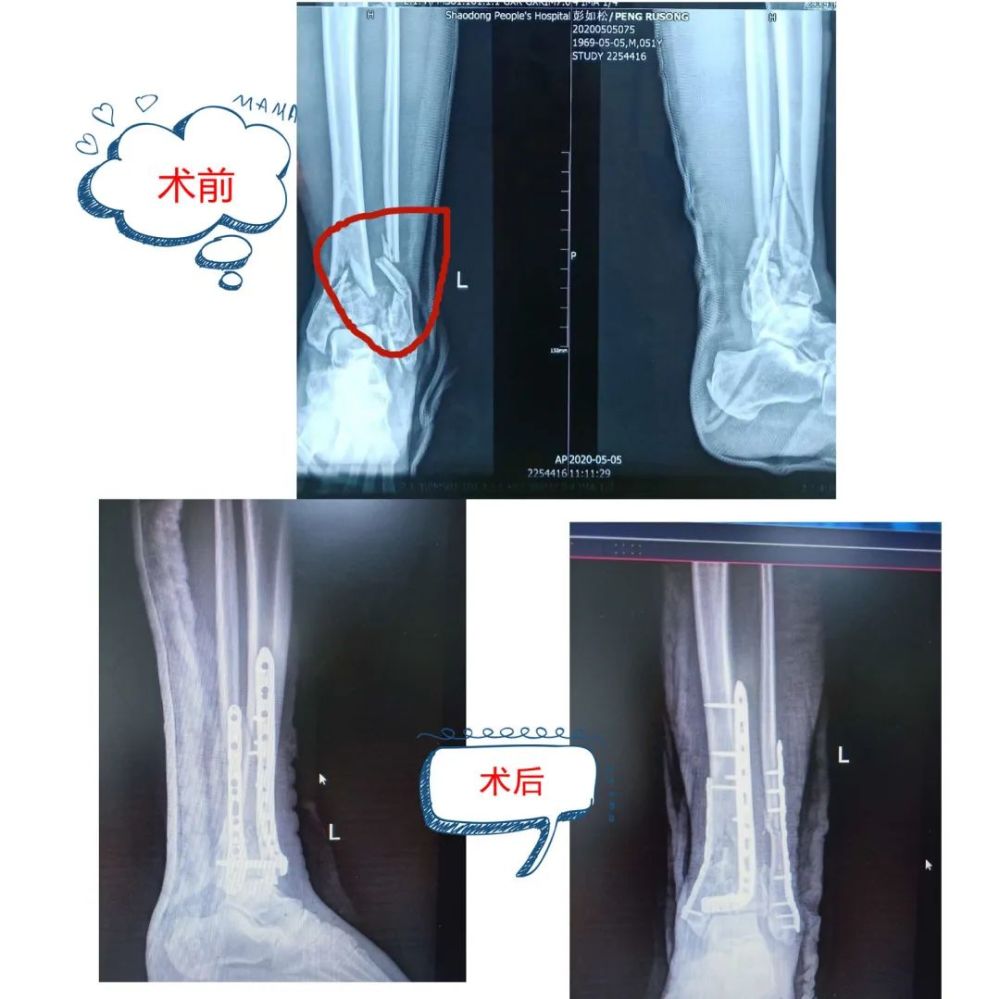

一例严重的胫腓骨远端粉碎骨折